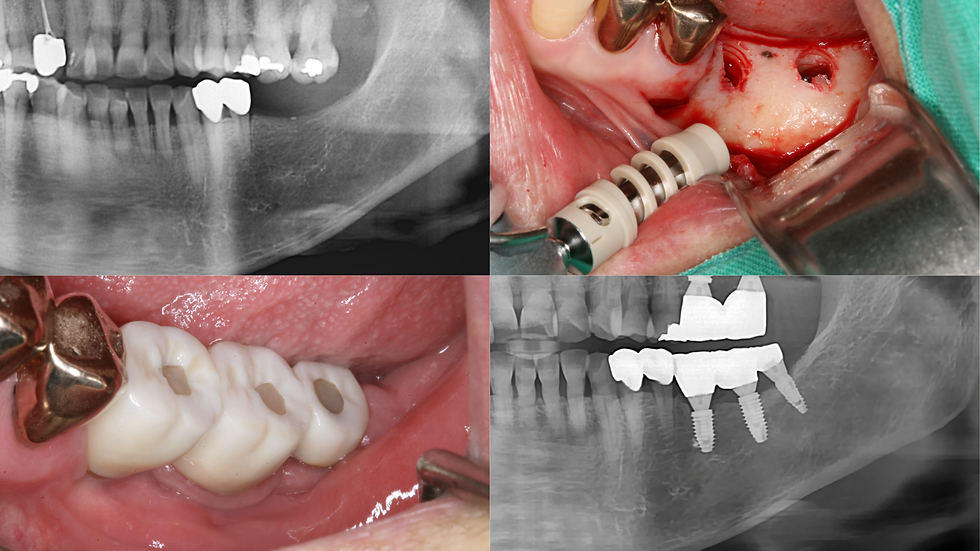

Pre-operative PA and intra-oral photograph

Step-by-step surgery

1) #25 IS-III 4.0*10mm, GBR, Healing abutment 5.0*5

2) Suture with 4-0 Nylon (Horizontal mattress suture)

* Initial stability: Good (25N)

* Bone quality: D2

Intra-oral photograph

Panorama and CT(sectioned) view